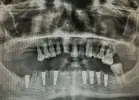

Implant Treatment